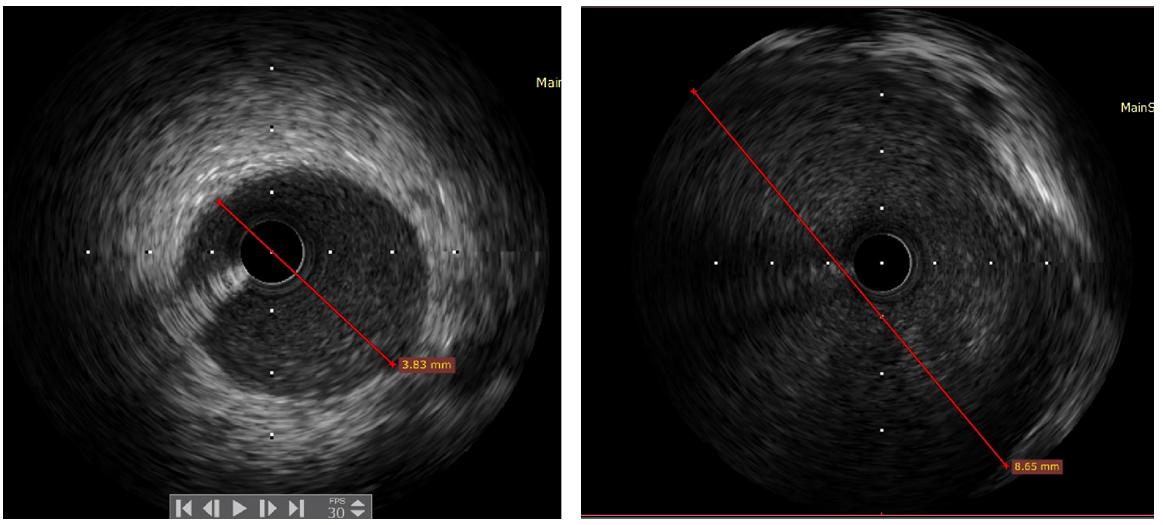

等药物后,冠状动脉血流得到改善,再次造影显示前降支近段存在一个巨大瘤样扩张(图3右)。行血管内超声

(IVUS)检查提示,冠状动脉并无粥样硬化斑块,前降支近段正常血管内径3.8mm(图4左),IVUS测量瘤样扩张血管内径约8.6mm(图4右),冠状动脉瘤诊断明确,未行支架置入术,安返病房。

图4左 IVUS测量前降支近段正常血管内径,约3.8mm;图4右 IVUS测量瘤样扩张血管内径约8.6mm